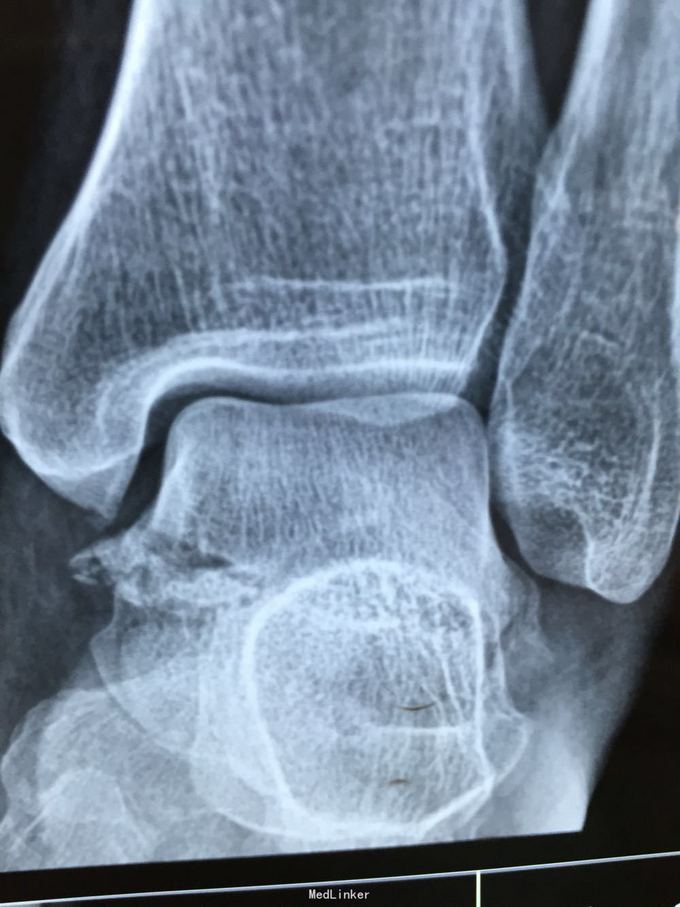

距骨骨折

患者因车祸致左足疼痛1小时入院

左足背肿胀明显,压痛

左距骨骨折